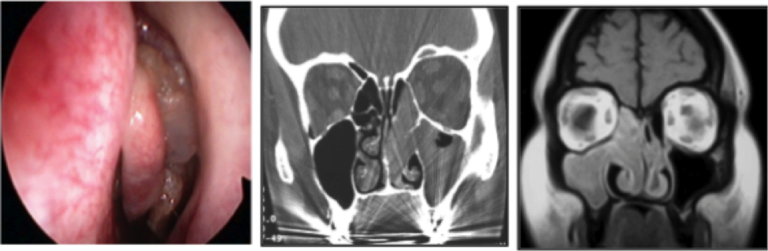

Sinusite batterica monolaterale: maxillectomia mediale endoscopica modificata

Sinusite Acuta Monolaterale: trattamento endoscopico rinosinusale

Maxillectomia mediale endoscopica per papilloma invertito del seno mascellare

Proteina S100 e Papilloma Invertito Nasosinusale

Papilloma invertito rinosinusale e recidive

HPV causa del Papilloma Invertito Rinosinusale?

Patologia Rinosinusale Monolaterale